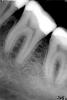

vuser Опубликовано 2 октября, 2013 Поделиться Опубликовано 2 октября, 2013 Добрый день! был на консультации и мне сказали что на 36 расширение периодонтальных щелей. Скажите это видно по снимку? Что-то мне кажется что после сохранения на флешку он чёткость потерял Ссылка на комментарий

x3m Опубликовано 2 октября, 2013 Поделиться Опубликовано 2 октября, 2013 знаете, похоже снимок преобразовали в серое 256 оттенковнет, ничего не преобразовывали.просто сбросили исходник из программы, но почему-то в формате .жпег ехать никуда не нужно, достаточно попросить прислать снимок в нормальном контрасте (можно даже как скриншот удобочитаемого снимка в оболочке программы) vuser, присмотритесь к сообщению №2.в целом, рентгенологически нет никаких ай-яй-яев в периодонте )) Ссылка на комментарий

x3m Опубликовано 2 октября, 2013 Поделиться Опубликовано 2 октября, 2013 (изменено) знаете, похоже снимок преобразовали в серое 256 оттенков"преобразовал" в родной программе и заскриншотил. так лучше? был бы .tif - получилось бы еще красивей по сути - ничего плохого я, например, не вижу.да, пломба/вкладка массивная... да, кариес был глубоким... да, недалеко от нерва в дальней части пломбы...но если не беспокоит и конструкция на зубе состоятельна - просто наблюдать. Изменено 2 октября, 2013 пользователем x3m Ссылка на комментарий

x3m Опубликовано 2 октября, 2013 Поделиться Опубликовано 2 октября, 2013 Остался вопрос по части прилежания пломбы к 35. Там всё хорошо или щель? Дело в том что когда я чистил флосом и вытягивал нитку было ощущение разрыва. Через 3 недели оно прошло, но иногда бывает, когда нитку просовываю. Или когда жую бывает. Доктор который ставил пломбу говорил1. кость сверлю уже, ничего не видно2. убирая нить "кровило зараза", "кровит сильно", "пломбу на низ поставил, наверх в следующий раз". Как бы это всё проверить окончально. Я ему жаловался, он сказал ничего не видит.вроде хорошо. но снимок не есть однозначным диагностическим инструментом. нить должна вводиться и выводиться со щелчком.БЕЗ чувства зацепа (где-то там внизу) и разволокнения/обрыва нити.ничего не понял, что бывает, когда сейчас просовываете/жуете =) 1. звучит нехорошо. все, что клеится к зубу, должно клеиться к сухой и чистой поверхности зуба (без крови, слюны и проч. жидкостей и загрязнений).2. это доктор "выдыхал" после интересной работы Вот тифф, его, пожалуйста преобразуйте "обратимый пульпит". После постановки через 3 недели ... начал ныть через 2 недели.Сейчас периодически,Ночных болей не было.На струю холодного реагирует. На постукивание - ничего.Так же возник вопрос, я заметил потемнение между пломбой на 35 и корнем, и со стороны 37 на 36 тоже но меньше. Вот на обработанном тиф что-то видно? Или это мелочи?преобразовал. магией в личке. как эти зубы реагируют на холод? так же, как и все остальные? болят после прекращения холода?пища часто застряет? как отдифференцировать "обратимый пульпит"? (вопрос к коллегам). пломбы довольно массивные, лучше такое восстанавливать керамическими вкладками/коронками. с правильным контактным пунктом между зубами, без нависающих над десной краев. потемнение говорит о вторичном кариесе (вероятно). Надо смотреть воочию. не видно ничего нового. В целом, реставрации достаточно точны по краю "пломба-зуб". Ссылка на комментарий